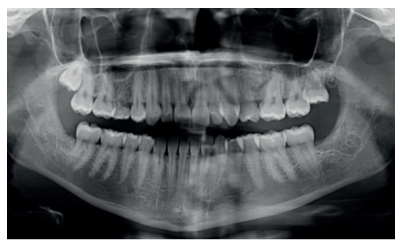

A los diez días se retiró la sutura (Figura 20), donde se puede observar una buena cicatrización de los tejidos blandos. A los 4 meses se realizó una revisión, clínica (Figura 21) y radiográfi ca, mediante radiografía panorámica (Figura 22) y un escáner de haz cónico (Figura 23), donde se puede apreciar la integración del material de injerto y una densidad ósea similar al hueso adyacente, derivando de nuevo a la paciente para comenzar el tratamiento ortodóntico.